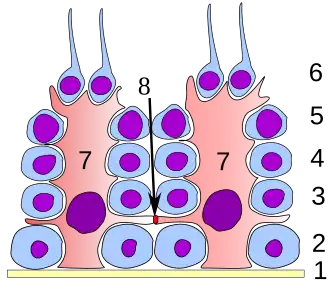

Germinal epithelium of the testicle. 1 basal lamina, 2 spermatogonia, 3 spermatocyte 1st order, 4 spermatocyte 2nd order, 5 spermatid, 6 mature spermatid, 7 Sertoli cell, 8 tight junction (blood testis barrier) | |

A spermatogonium (plural: spermatogonia) is an undifferentiated male germ cell. Spermatogonia undergo spermatogenesis to form mature spermatozoa in the seminiferous tubules of the testicles.

Spermatogenesis

Spermatogenesis is the process in which sperm cells are produced and formed into mature spermatozoa from spermatogonia. Males mature spermatozoa (sperm) are produced to later join with a female oocyte (egg) to create offspring. Throughout the process of spermatogenesis, there are many different parts of the male anatomy, accessory organs, and hormones. However, spermatogenesis can be broken down in the following steps, which are initiated at the start of puberty:

- Spermatogenesis occurs in the germinal epithelium of the seminiferous tubules. Spermatogonia undergo meiosis to produce spermatids that later mature into spermatozoa. The spermatogonia duplicate their DNA to obtain 46 chromosomes in preparation for the primary division. At this stage, the germ cells are now referred to as primary spermatocytes. [3]

- The primary spermatocytes undergo a primary division, yielding two secondary spermatocytes each with 23 chromatids. The secondary spermatocytes then undergo a second division to produce two spermatids, each with 23 chromosomes. [3]

- The spermatids are currently surrounded by Sertoli cells, which nourish the sperm and produce inhibin, an inhibitor of the follicle-stimulating hormone (FSH).[3]

- The last step of spermatogenesis is spermiogenesis. During this process, the spermatids are transformed into spermatozoa, mature sperm. At this point, no other division occurs. The sperm is released from the Sertoli cells and transported to the epididymis through peristalsis. While in the epididymis, the sperm is stored and begins maturation. Once the sperm has fully matured, it will reach its spermatozoan phase.[3]